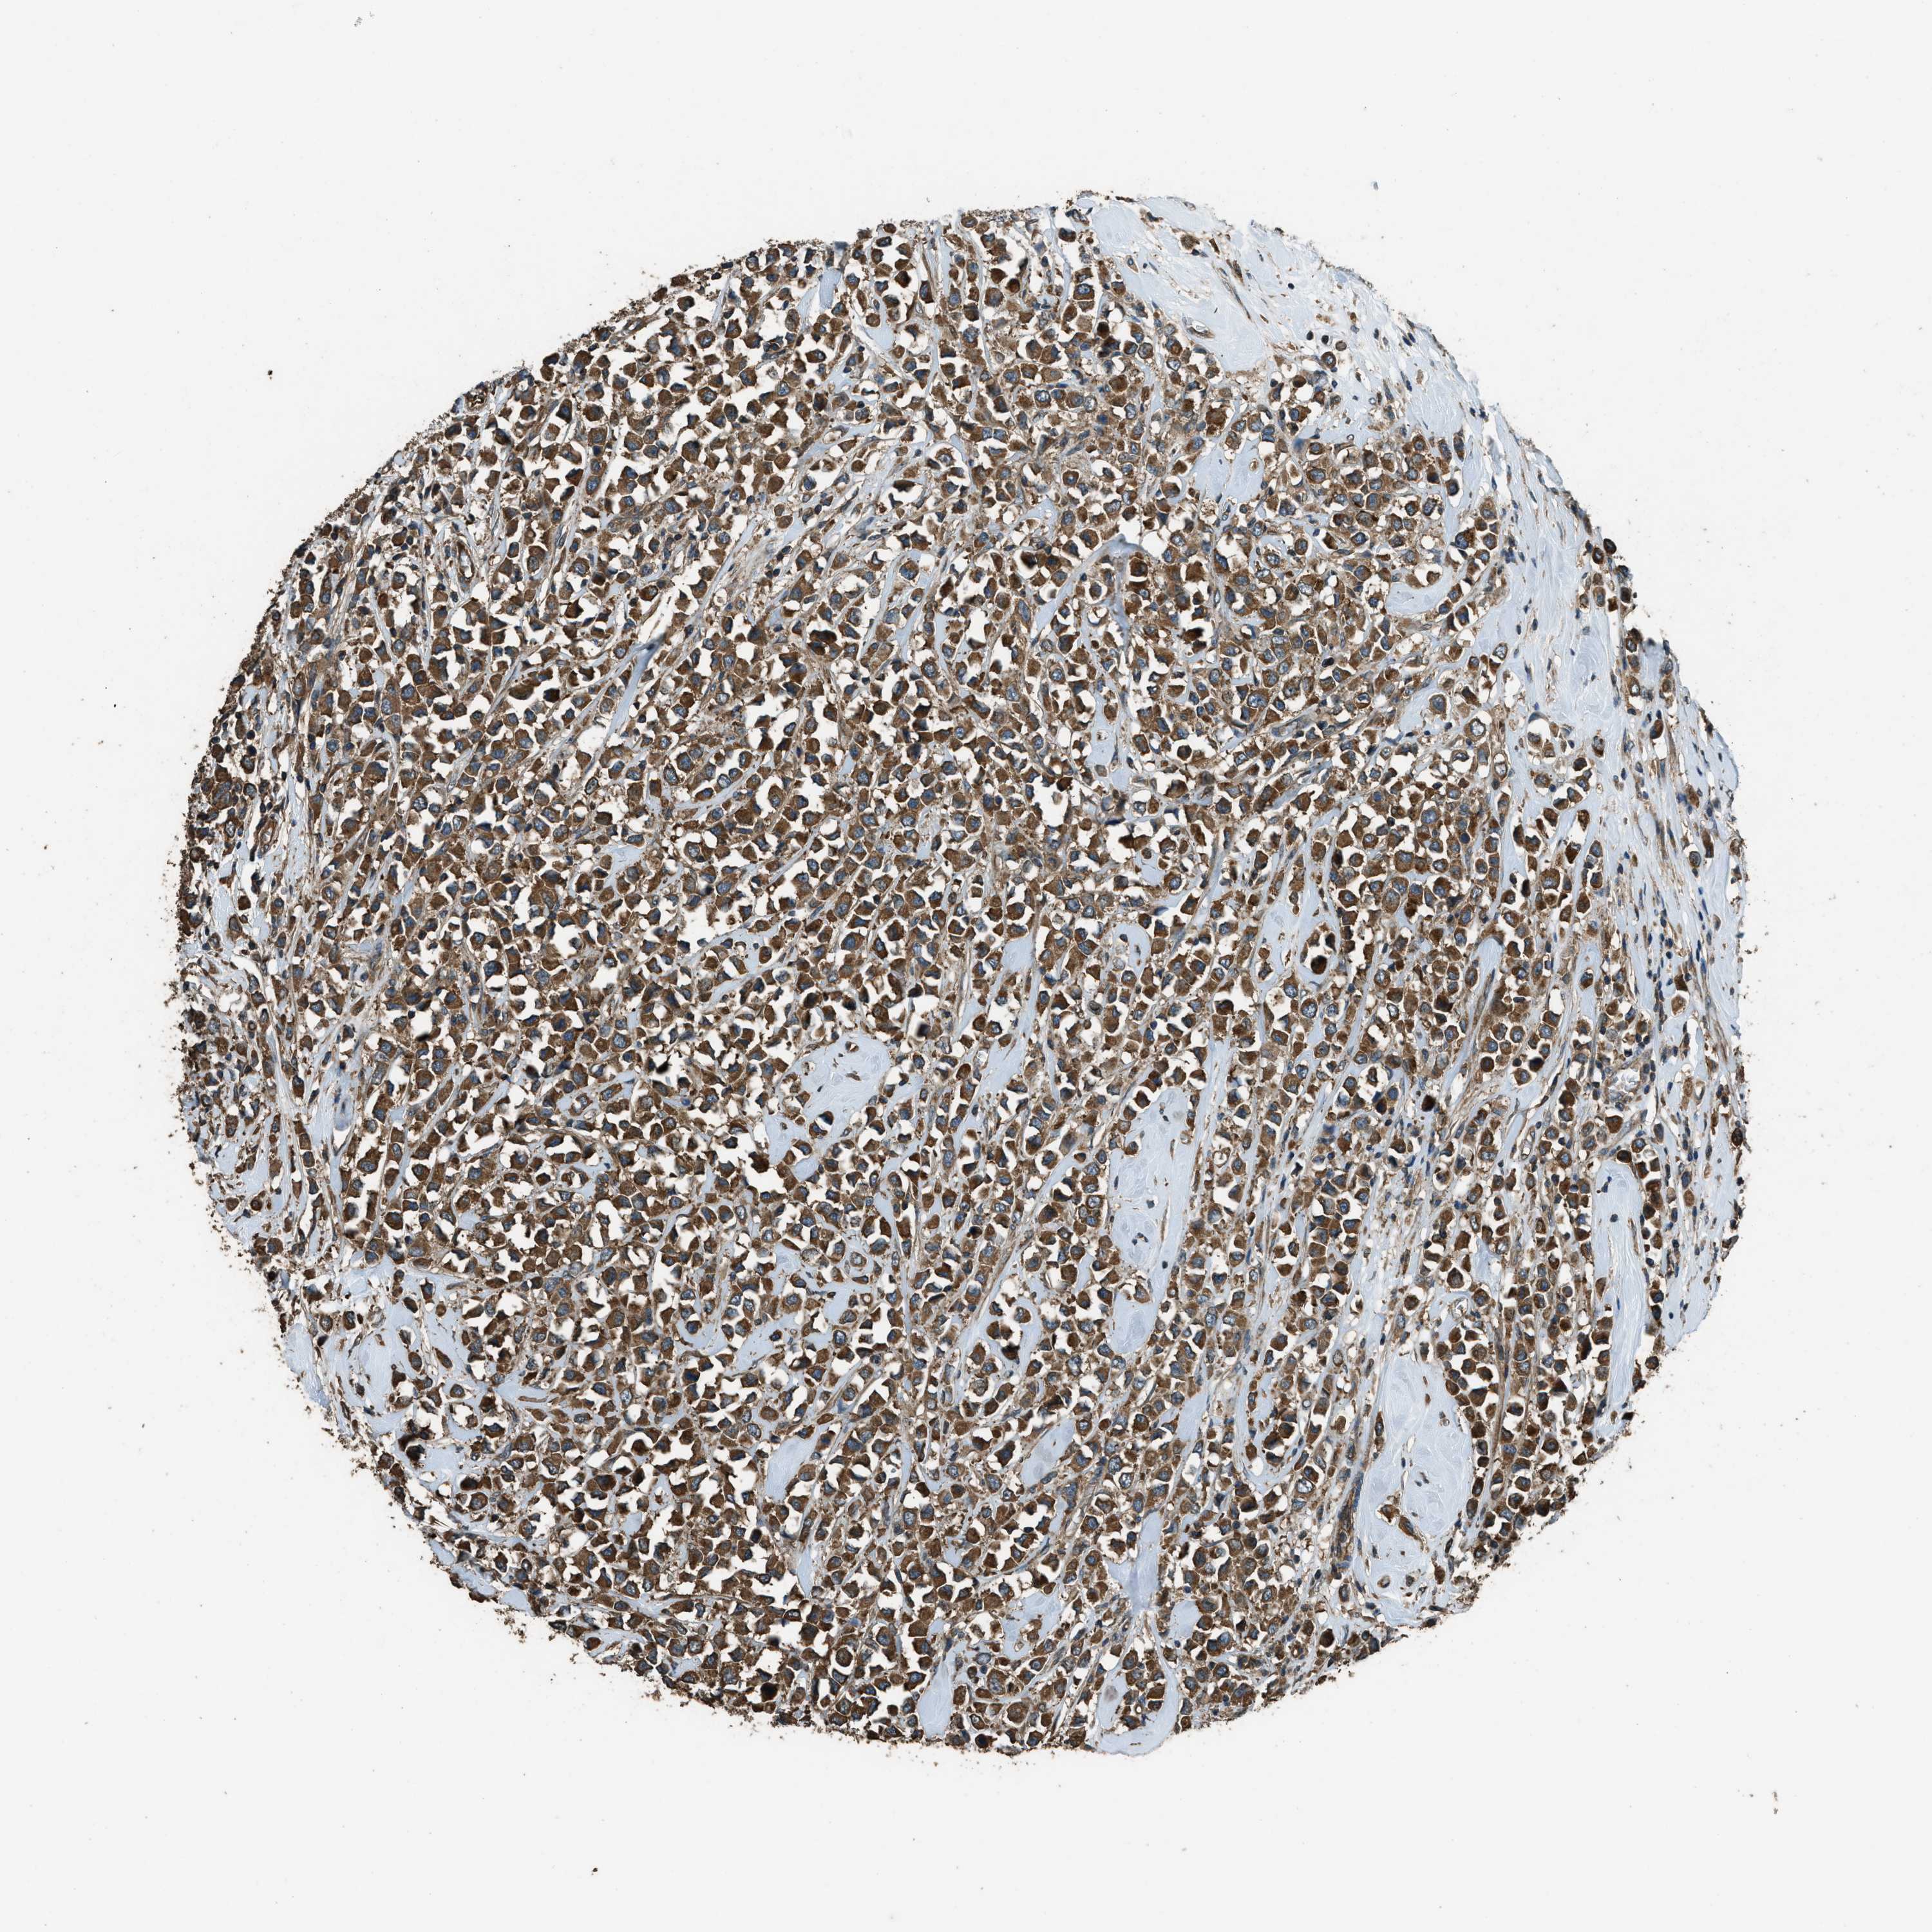

BRCA TCGA BRCA VALIDATION PROTEIN EXPRESSION

ANTIBODIES

AND

VALIDATION